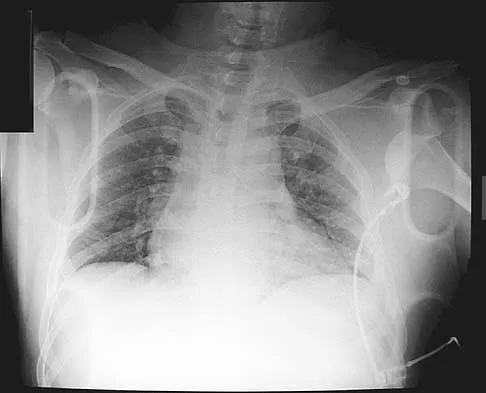

Figure 11 shows the radiograph of a 26-year-old man with type I diabetes mellitus who was struck by a motor vehicle. What is the most common complication associated with this pelvic fracture?

Explanation

The most common complication following acetabular or pelvic ring injury is deep venous thrombosis (DVT). Without prophylaxis, rates of DVT are as high as 70% to 80%. With prophylaxis, the rates are around 10%. Infection rates in surgical repair of acetabular fractures are relatively low but a history of diabetes mellitus and a significant Morel-Lavalle lesion certainly increase the risk. However, even with these two complicating factors, the rates of infection are still lower than 10%. Sciatic nerve palsy rates from the injury alone approach 20% and iatrogenic injury is usually less than 2%. Degenerative changes to the hip following this injury approach 20% to 25%, even with an anatomic reduction. Geerts WH, Code KI, Jay RM, et al: A prospective study of venous thromboembolism after major trauma. N Engl J Med 1994;331:1601-1606.